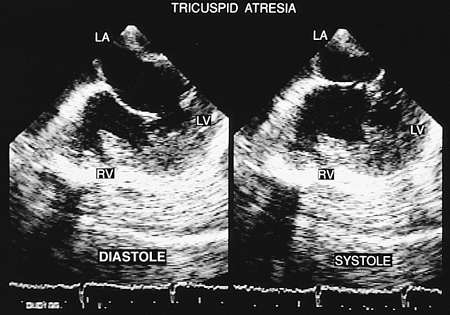

Right-sided absence, or classic tricuspid atresia, is characterized by a lack of continuity between the right cavities. The floor of the right atrium is muscular and is separated from the right ventricle by fibrous tissue from the A–V sulcus. There are rare cases of true tricuspid atresia in which the right chambers have a potential connection through an imperforate valvular membrane.

In patients with the absence of right A–V connection (classic tricuspid atresia), the signs discussed in the following paragraphs can be observed with transesophageal echocardiography.

Absence of the movement of the tricuspid valve can be seen, with ample diastolic mobility of the mitral valve (Fig. 8.2.33). In the four-chamber image a line of dense echoes can be seen below the right atrial floor, which represents the fibrous tissue of the A–V sulcus (Fig. 8.2.34). The presence of a small right ventricle and a dilated and hypertrophied left ventricle is confirmed by biplanar transgastric and transesophageal recordings.

Because of the loss of alignment of the interatrial and interventricular septa resulting from anterior displacement of the interventricular septum, the right atrium can be seen to project to a greater or lesser degree on the left ventricle in four-chamber images (Fig. 8.2.35). Color-coded Doppler recordings show the obligatory atrial septal defect (Fig. 8.2.36). In cases in which one of the great vessels is connected to the rudimentary ventricle, a defect of the trabecular portion of the ventricular septum also can be identified. Doppler spectral analysis aids in detecting possible gradients through the septal defects when one of these is restrictive. Atrioseptostomy is indicated when an important gradient is generated through the atrial septal defect.